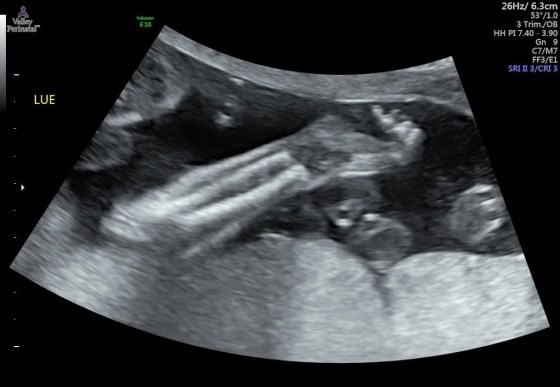

And last but not least, pictures of baby brother! Isn’t he already cute??